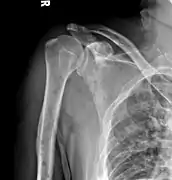

The diagnostic examination of a person with suspected multiple myeloma typically includes a skeletal survey. This is a series of X-rays of the skull, axial skeleton, and proximal long bones. Myeloma activity sometimes appears as "lytic lesions" (with local disappearance of normal bone due to resorption). And on the skull X-ray as "punched-out lesions" (raindrop skull). Lesions may also be sclerotic, which is seen as radiodense.[59] Overall, the radiodensity of myeloma is between −30 and 120 Hounsfield units (HU).[60] Magnetic resonance imaging is more sensitive than simple X-rays in the detection of lytic lesions, and may supersede a skeletal survey, especially when vertebral disease is suspected. Occasionally, a CT scan is performed to measure the size of soft-tissue plasmacytomas. Bone scans are typically not of any additional value in the workup of people with myeloma (no new bone formation; lytic lesions not well visualized on bone scan).

Multiple myeloma in the upper arm